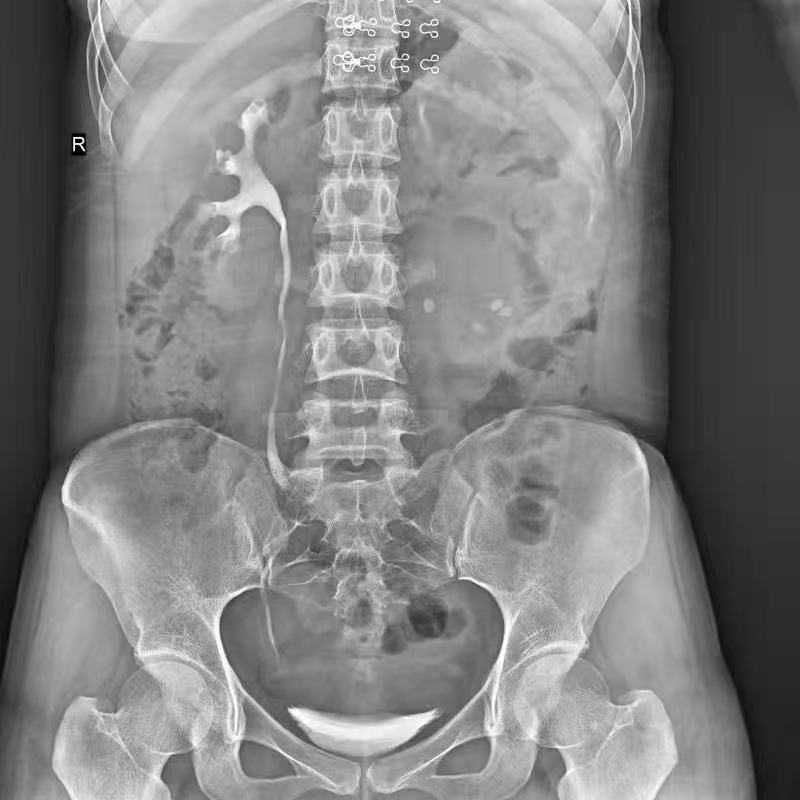

普利德醫療自主研發(fā)的新一代數字化X線(xiàn)透視攝影系統,可應用于DR攝影、數字透視、數字造影以及可視化精準DR拍片等多種臨床X線(xiàn)檢查領(lǐng)域。

● 17*17英寸的超高清像素動(dòng)態(tài)平板探測器,更大的視野范圍,無(wú)需移動(dòng)即可觀(guān)察整個(gè)動(dòng)態(tài)過(guò)程,避免拖尾、噪聲對圖像的影響;

● 高效動(dòng)態(tài)平板技術(shù),圖像不會(huì )有幾何畸變,提供高分辨率和精確的圖像,為醫生臨床診斷提供精準依據;

● 最高幀速可達30幀/秒,動(dòng)態(tài)采集清晰流暢,避免漏診、誤診情況的發(fā)生;

● 在可視過(guò)程或回放過(guò)程中,如發(fā)現疑似病灶,可進(jìn)行毫秒級高清點(diǎn)片,隨時(shí)抓取單幀圖像,精準捕抓病灶。